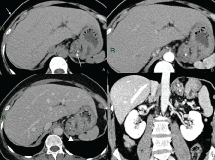

Figure 1: Contrast enhanced CT: Lesion of the gastric fundus Non-enhanced CT (A), arterious phase (B), venous phase (C) and coronal reconstruction (D) showing multiple small, clustered cystic foci combined in a lesion not dissociable from the gastric fundus (arrowhead in C). Two calcifications are well visible (arrow in A). View Figure 1

Figure 2: Contrast enhanced CT: Periduodenal lesion Non-enhanced CT (A), arterious phase (B), venous phase (C) and coronal reconstruction (D) Venous phase demonstrating clustered small cysts conjoined in periduodenal region (arrows in C and D). View Figure 2